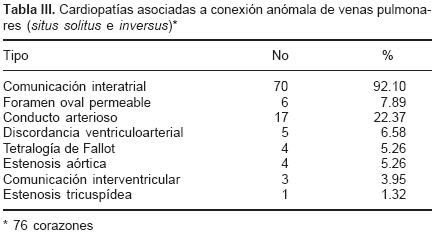

En el grupo mixto el trayecto de los colectores provenientes de cada pulmón dependió de los sitios de conexión anómala (Tabla II). Los setenta y tres corazones en situs solitus e inversas presentaron un defecto septal interatrial de tipo orificio oval (Figs. 2, 4, 7 y 9), mientras que en los treinta corazones con dextroisomerismo existió un atrio común y una bandeleta septal interatrial que separó dos grandes comunicaciones (Fig. 11). Todos los corazones presentaron dilatación de las cámaras derechas, del tronco y ramas de la arteria pulmonar así como hipertrofia del ventrículo derecho (Fig. 12). Respecto a las cámaras izquierdas el atrio fue pequeño e incompleto por carecer del SVP (Fig. 2), el ventrículo izquierdo y la válvula mitral tuvieron características normales. Las cardiopatías asociadas en los setenta y seis corazones con situs solitus e inversus se consignan en la Tabla III. Los treinta corazones con dextroisomerismo presentaron un patrón complejo de asociación de anomalías intracardíacas y vasculares (Tabla IV); en las Tablas V y VI se muestran respectivamente los tipos de conexión atrioventricular y ventriculoarterial en dextroisomerismo.